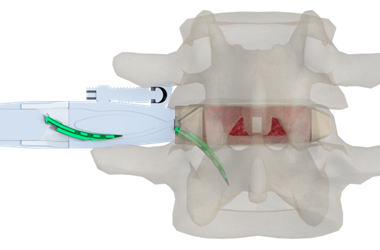

優(you)選(xuan)病例:Uni-L插片(pian)式自穩(wen)定型腰椎融(rong)合器(qi)

插片式自(zi)穩(wen)定腰(yao)椎融合(he)器應用(yong)于前次(ci)融合(he)手術失敗及(ji)鄰椎病(bing)。